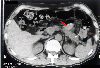

A case of colonic stenosis mimicking an advanced cancer in which pancreatitis involved the left colon(1980's).

CT

Tumor-like lesions/Invasion from neighbouring organ or tissue